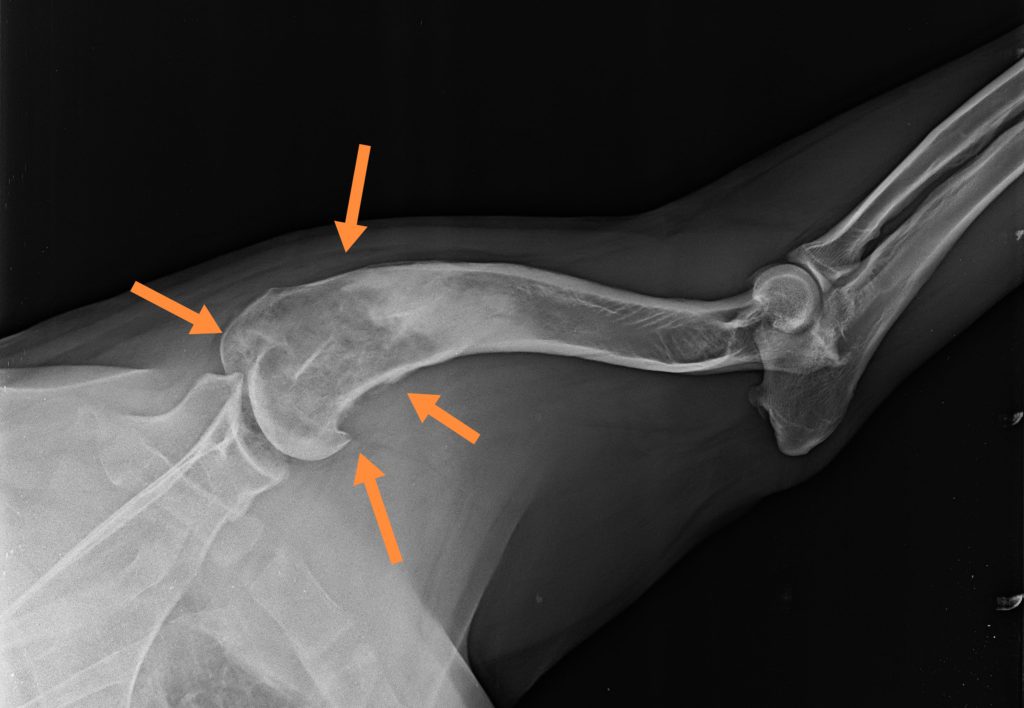

Krónikus, gyógyszerrezisztens sántaságnál, tapintható csontkemény duzzanat esetén a régió röntgenvizsgálata javasolt első körben. Az osteosarcoma (vagy más csontdaganat) esetén a csontok állománya felhőszerűen megritkul, a röntgeneken kissé molyrágtának tűnik, ezzel egyidejűleg a külső felszínen csontfelrakódások is kialakulnak, a csonthártya pedig sokszor elemelkedik, ami nagyon jellemző az osteosarcomára.

Erősen meggyengült csontszerkezet esetén annak patológiás törése, beroppanása is látható lehet. A röntgenfelvételeken látható csontoldódással járó elváltozások fertőző- vagy rosszindulatú folyamatra utalnak, ezért minden esetben további diagnosztikai vizsgálatok javasolhatók.